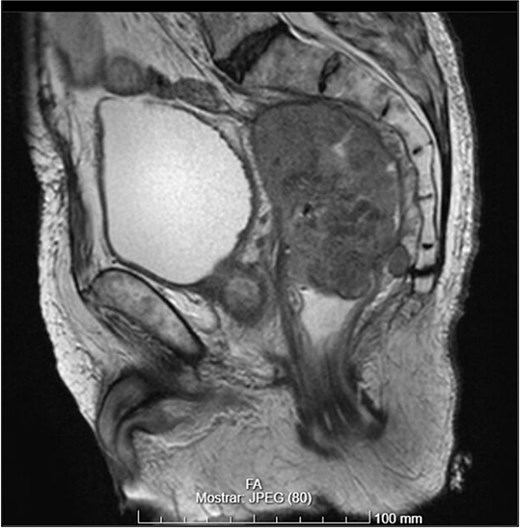

Pelvic magnetic resonance imaging (MRI) revealed a extrarectal lesion located 8 cm from the anal verge, with 4 × 4 cm, suspicious of tumoral deposit in the mesorectum (Figs 5 and 6).

- A mass measuring 9 × 8 cm near the rectal stump, consistent with tumor recurrence (Figs 8 and 9);